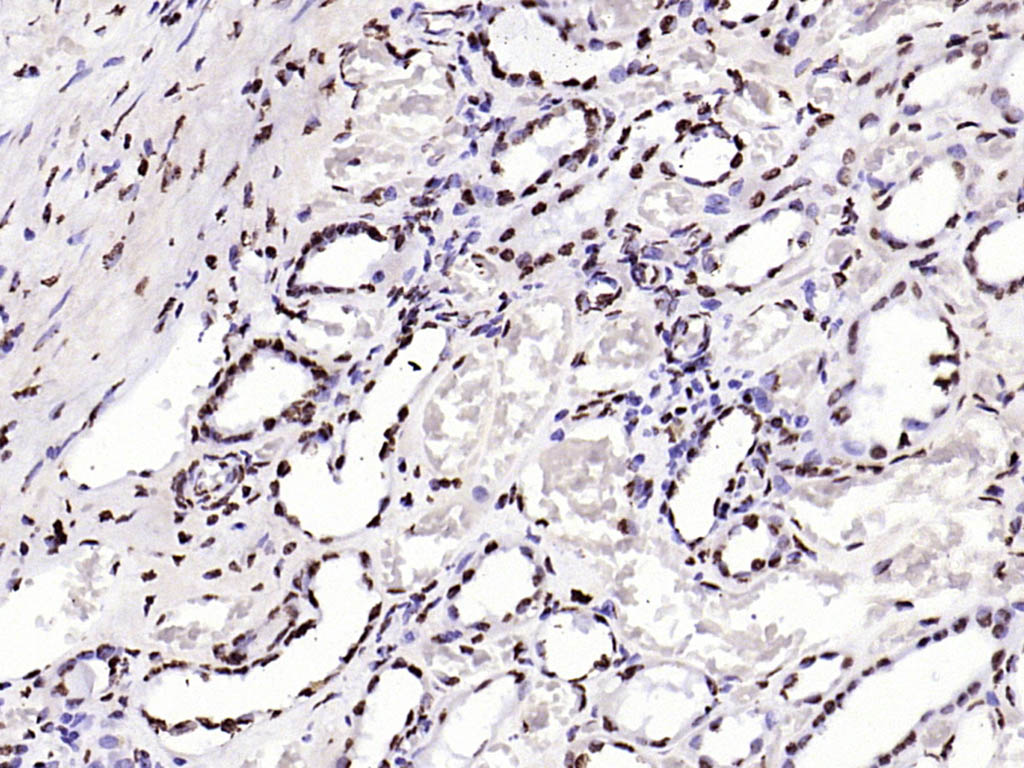

| 产品应用 | WB=1:200-1000, IHC-P=1:100-400, IHC-F=1:100-400, ICC/IF=1:100-500, IF=1:100-500, ELISA=1:5000-10000 Not yet tested in other applications. |

| {IHC-P} | {1:100-400} |